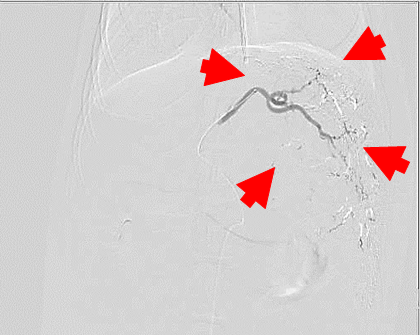

【診断・治療方針】

腹腔内腫瘤の破裂による非外傷性出血

― 腹腔内腫瘤は肝尾状葉由来 (Φ5cm)

腫瘤は動脈相で早期膿染

― 肝動脈尾状葉枝が栄養血管

オーナーと相談の結果、まずは腫瘤からの出血の制御を目的として第3病日にTAE(*)を実施する事となった。

TAE

腹腔動脈選択~腹腔動脈造影

総肝動脈選択~feeder選択

塞栓剤注入

ジェルパート1mm 粒(日本化薬)